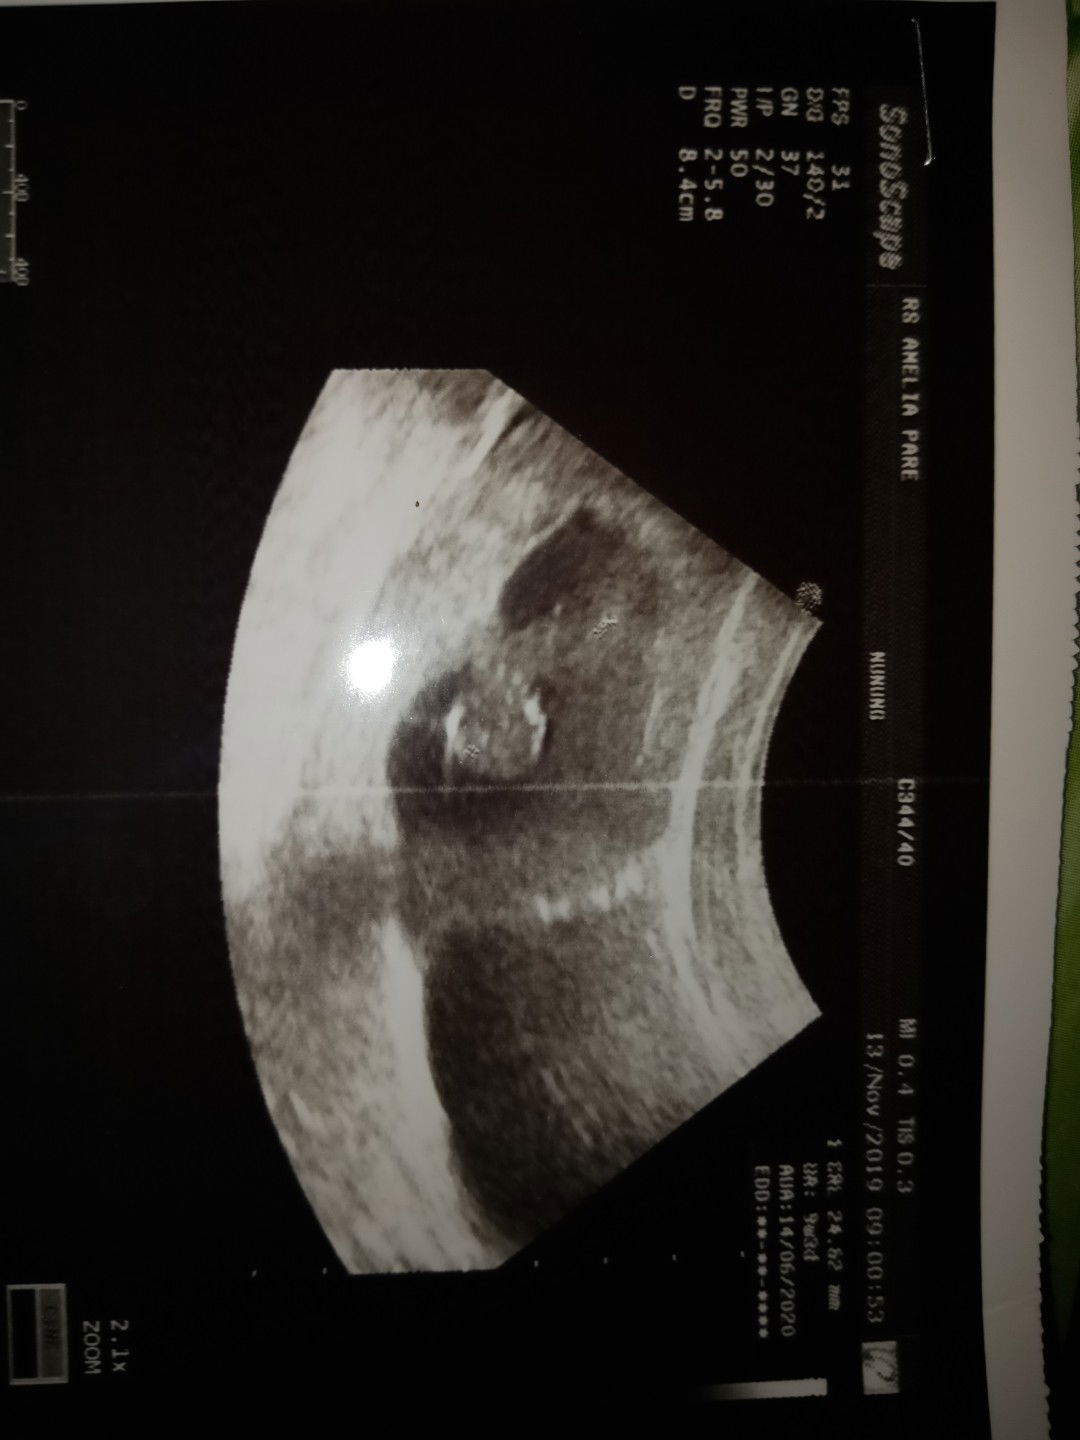

ratu of 1 enerjik anak laki-laki

Maaf bun mau minta saran, saya hamil sdah 3 bulan tpi kemarin sya pendarahan dan waktu d usg janin saya kata dokter denyut jantung nya tidak pasti.. Mohon saran nya bun untuk mempertahankan soal nya bilang nya dokter sya kandungan lemah trimakasih

Gimana cara nya supaya janin dalam kandungan kembali kuat dan sehat